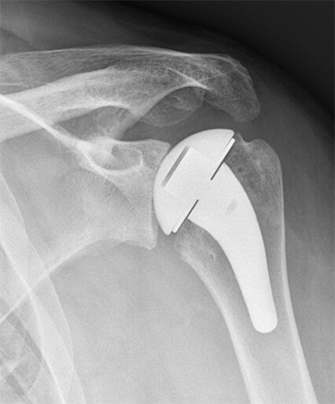

Pyrocarbon shoulder hemiarthroplasty

- Case Examples from Dr. Lee’s practice:

- This is a case example of a patient in his 40s who presented to us with severe shoulder pain, inability to work out and even raise his shoulder to chest level! At 6 months postoperatively he is back to the activities that he wants, keeping him active and healthy again